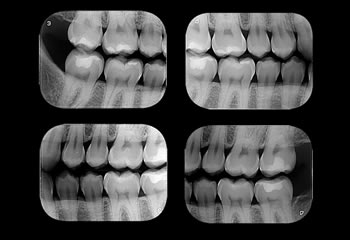

Radiografias Interproximais

Técnica radiográfica intrabucal, também conhecida como bitewing, é indicada principalmente para molares e pré-molares na avaliação de cáries, restaurações e cristas ósseas alveolares.